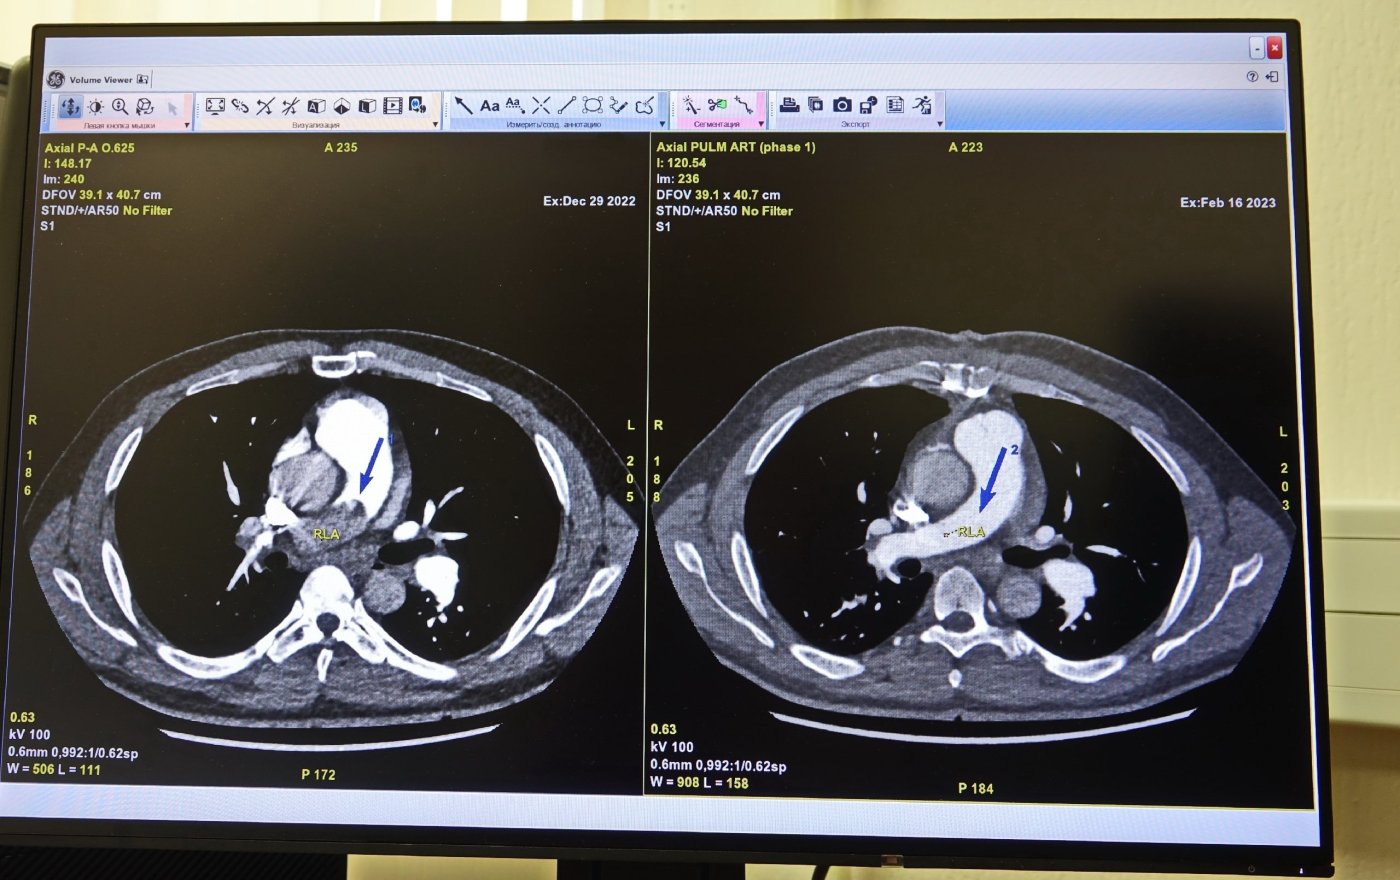

Одышка, слабость, сухой кашель — с такими симптомами в больницу поступил сургутянин 49 лет. Жалобы у мужчины усугубились после перенесенной коронавирусной инфекции и пневмонии в 2021 году. Симптомы постепенно нарастали. Диагностический поиск привел к разгадке. На компьютерной томографии врачи обнаружили массивный тромб, который занял почти все пространство правой легочной артерии, частично левой, и фактически изолировал часть легких от кровоснабжения.

Просвет правой легочной артерии полностью перекрывал тромб. Сердце, несмотря на это препятствие, продолжало выполнять свою работу, но уже с большим усилием. Состояние мужчины ухудшалось.